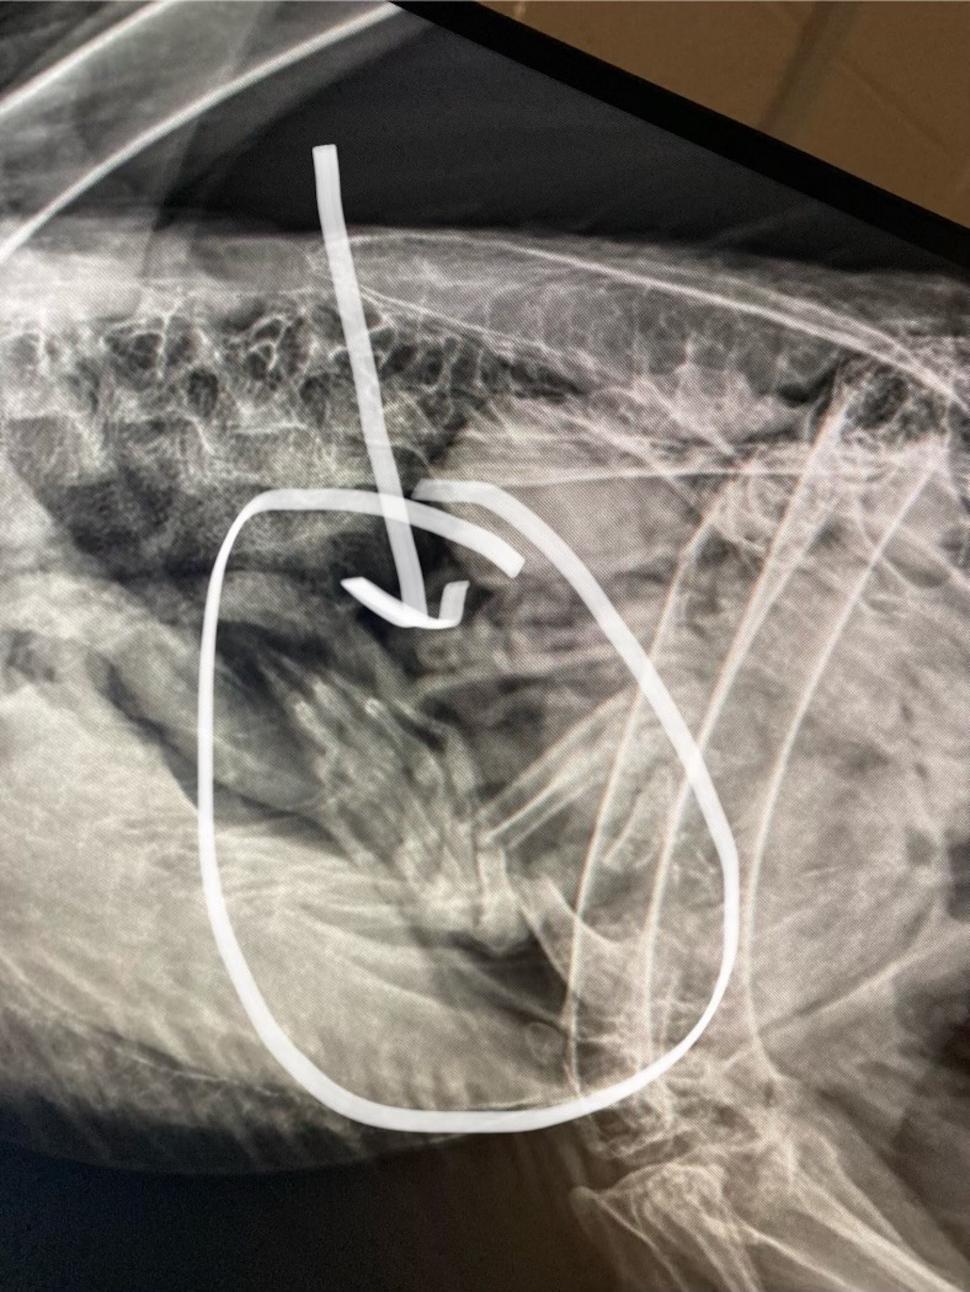

Radiografiile realizate la Grădina Zoologică Dickerson Park au confirmat suspiciunile: vulturul mâncase atât de mult, încât nu mai putea să-și ia zborul. Imaginile arătau clar conturul unui raton în stomacul păsării, cel mai probabil o pradă găsită moartă pe marginea drumului.

„Radiografiile furnizate de Grădina Zoologică Dickerson Park arată conturul a ceea ce suspectăm a fi un raton găsit mort pe marginea drumului.”